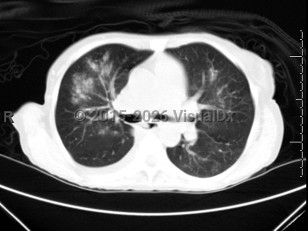

COVID-19